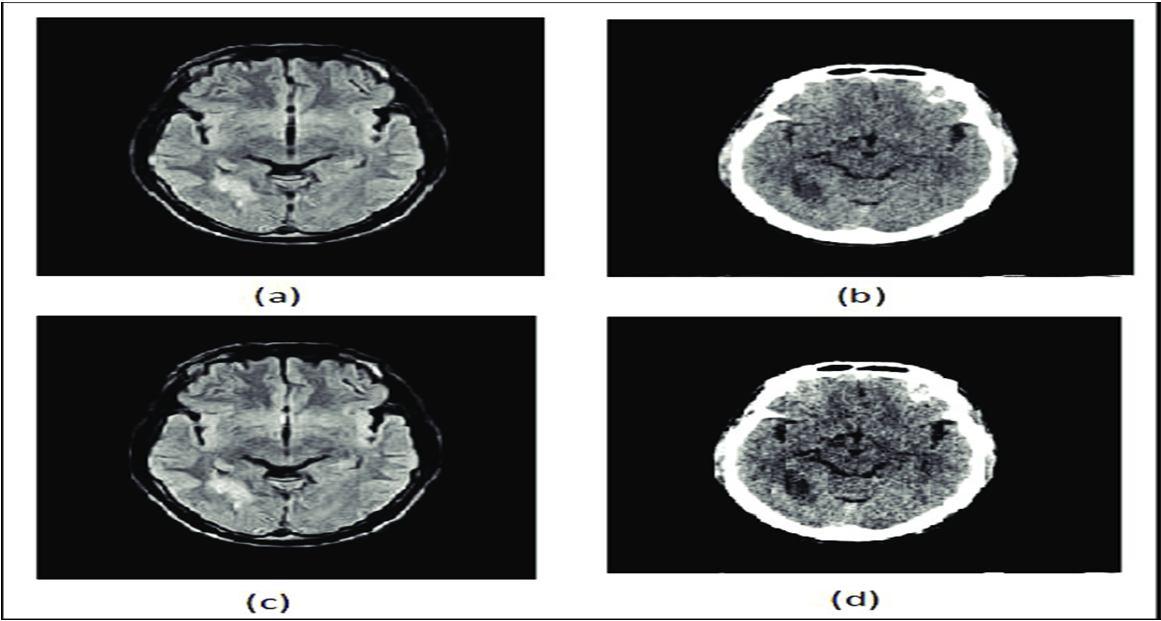

The median filter is a nonlinear filter that is used for removing noise from the images. It is very effective at removing impetus noise, the “salt, and pepper” noise, in the image. The principle of the median filter is to substitute the gray level of each pixel with the median of the gray levels in a neighborhood of the pixels, instead of using the average operation. The median filter used for removing salt and pepper noise from MRI images is shown in figure 2

Fig. 1 Block diagram of feature extraction through Digital Image processing Fig 2. (a) And (c) original images and (b) and (d) after noise removal by median filter

Noise removal techniques have become a necessary practice in medical imaging applications for the study of anatomical structure and image processing of MRI medical images. To report these issues, many de-noising algorithms have been developed like the Gaussian filter, Weiner filter, median filter, etc. The most commonly affected noises in medical MRI images are Speckle, Salt and Pepper, Gaussian, and Poisson noise. The medical images taken for comparison include MRI images, in grayscale as well as RGB.